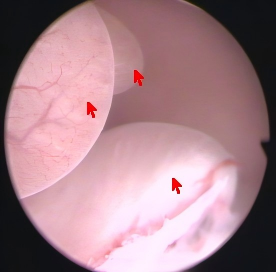

近日,44岁的王女士因 “阴道不规则流血 8 天” 入住我院妇科,经详细检查,术前诊断为多发性子宫内膜息肉,既往有宫腔镜子宫内膜息肉切除手术史。7月4日,妇科团队为其进行宫腔镜检查,发现宫腔深11cm 且存在多发性子宫内膜息肉及宫颈息肉。在吕晓亮主任医师的主刀下,顺利完成了宫腔镜下子宫内膜息肉切除术及宫颈息肉切除术。

曼月乐环作为指南推荐的子宫内膜息肉术后的长期管理药物之一,一次放置有效期可达5年,具有良好的依从性和经济性。然而,王女士宫腔深度较大,传统方法放置曼月乐环存在下移和脱落风险。为确保治疗效果,我院妇科团队经过详细评估,决定采用宫腔镜下曼月乐环盘扣法固定术。在手术室和麻醉医生的密切配合下,手术顺利完成,患者术后恢复良好,第一天即痊愈出院。